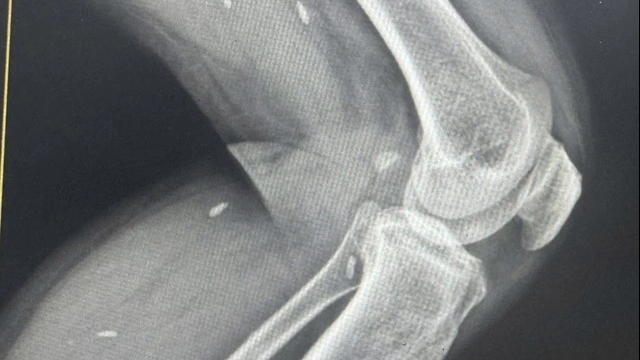

| Hình ảnh vết rắn cắn ở ngón cái bàn tay phải bị sưng đỏ, có dấu hiệu hoại tử. Ảnh: Mai Thanh/bachmai.gov.vn |

Trường hợp thứ hai bị rắn hổ mang cắn là anh Nguyễn Văn Đ (41 tuổi, ở Khoái Châu, Hưng Yên). Trong khi dọn đống gạch cũ lâu ngày, anh đã bị một con rắn hổ mang cắn vào ngón tay trên bàn tay phải. Sau đó, bệnh nhân có garo và nặn máu vết cắn. Vị trí bị cắn sưng đau nhiều, tấy đỏ. Sau khi được chuyển đến Bệnh viện Đa Khoa tỉnh Hưng Yên, bệnh nhân được truyền dịch, SAT và được chuyển đến Trung tâm Chống độc, Bệnh viện Bạch Mai.